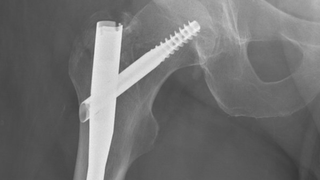

Aging; Orthopaedics

Why hip fractures require immediate treatment

UT Southwestern discusses the risks of delaying hip fracture treatment after a fall, especially for the elderly.